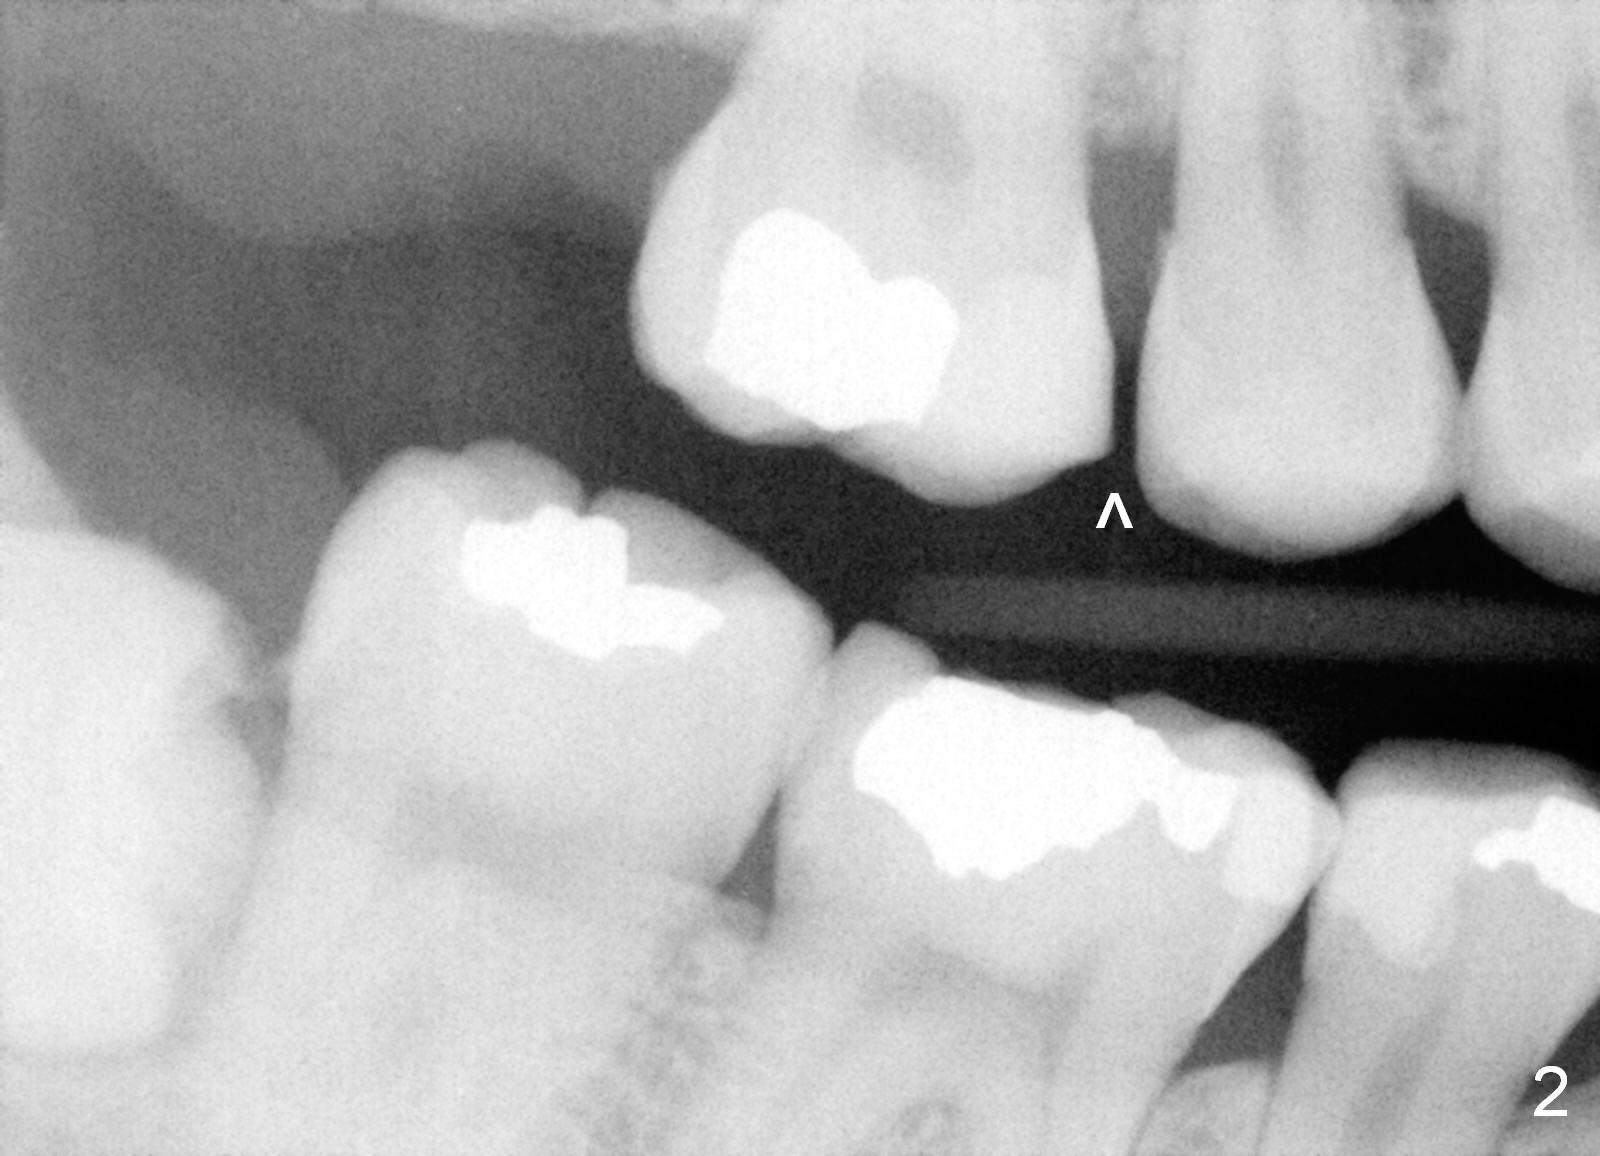

The panoramic X-ray (Fig.1) was taken on 12/12/2011 when the teeth #15 and 16 were extracted. The teeth #1 and 2 were removed half a year later. Bitewings (Fig.2-5), PAs (Fig.6,7) and upper occlusal mirror photo were taken on 02/11/2015. Pay attention to Fig.2.